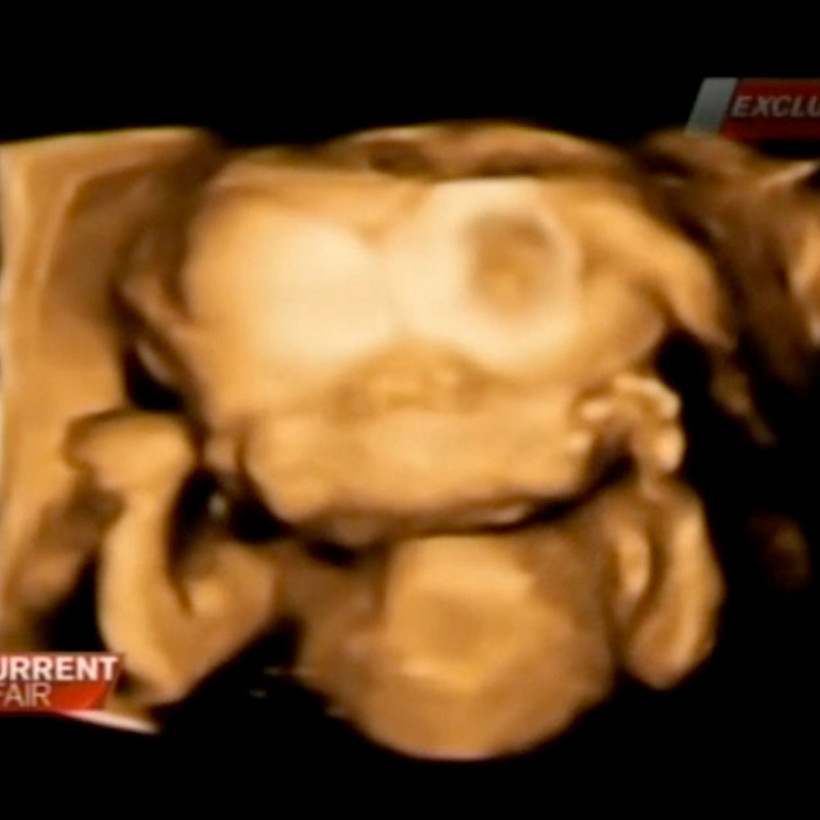

Οι υπέρηχοι έδειξαν πως το παιδί έχει δύο πόδια, δύο χέρια και ένα σώμα με όλα τα ζωτικά όργανα, συμπεριλαμβανομένης μίας υγιέστατης καρδιάς. Στο κρανίο, όμως, υπάρχουν δύο διαφορετικά πρόσωπα και δύο εγκέφαλοι ενωμένοι.

Οι γιατροί στην Αυστραλία μιλούν για μία πολύ σπάνια περίπτωση σιαμαίων: «Θα έλεγα είναι μία στο ένα ή δύο εκατομμύρια», δήλωσε χαρακτηριστικά ο Γκρεγκ Κέσμπι.